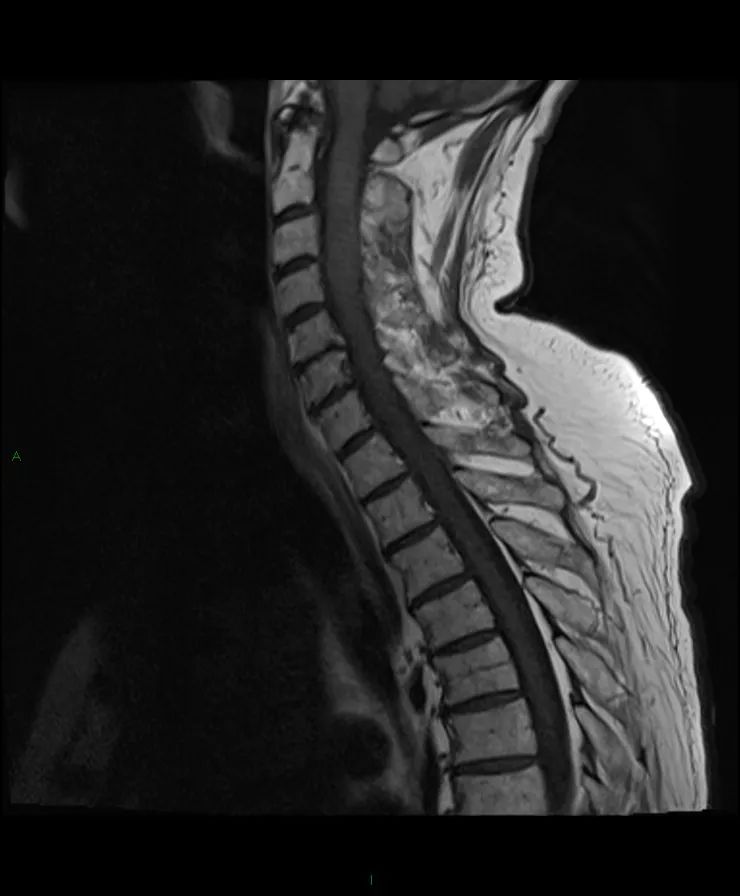

【病例】脊髓星形细胞瘤1例MR影像-3

颈脊髓在C2和T1之间肿块,T1等信号,T2高信号,不规则的非均匀强化。